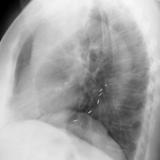

LULobectomy ex 2

Date: 07/23/2006

Views: 2996

Views: 2973

Views: 3714